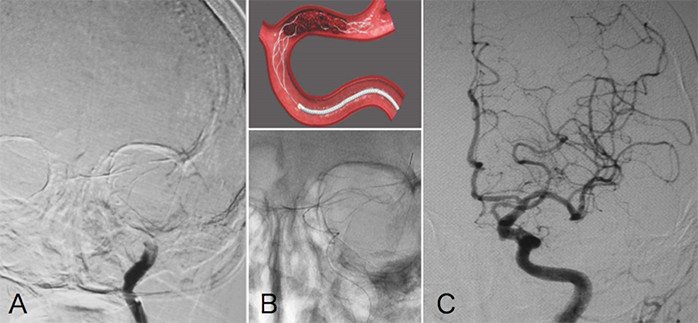

カテーテルによる血栓回収

脳内の太い血管がつまる症例などでは、血栓溶解療法(rt-PA)は十分な結果が得られないことも多く、そうした場合に行われるのが血栓回収治療です。カテーテルと呼ばれる細い管を血管内に挿入し、血栓がつまっている箇所まで運びます。その後に、カテーテルを通じて治療機器を操作し、血栓を絡めとる、もしくは吸引して回収します。

左内頸動脈閉塞の治療例

カテーテル治療により回収された血栓